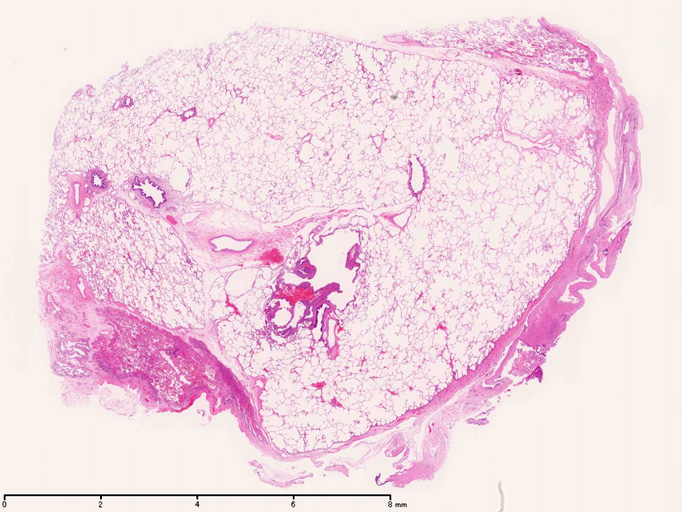

LAMの肺病変

嚢胞周囲または肺血管, リンパ管, 細気管支にそうLAM cellの浸潤, 集簇を特徴とする。LAM cellには2種類が認められ, 小型紡錘形細胞と細胞質の豊富な類上皮様細胞があり, 紡錘型は主に集簇巣の中心に存在し増殖能が高い。 類上皮様LAM cellは辺縁部に多く, 増殖能は低いがHMB45を強く発現している。

LAM cellの免疫染色--SMA, desmin, vimentin(vimentinはいつも陽性とはならない)が陽性となりmuscle lineageであるが典型的な筋細胞と異なり,

嚢胞形成はLAM cellの増殖と関連しており, 細胞が産生するmatrix metalloproteinases(MMPs)による組織破壊によるらしい。